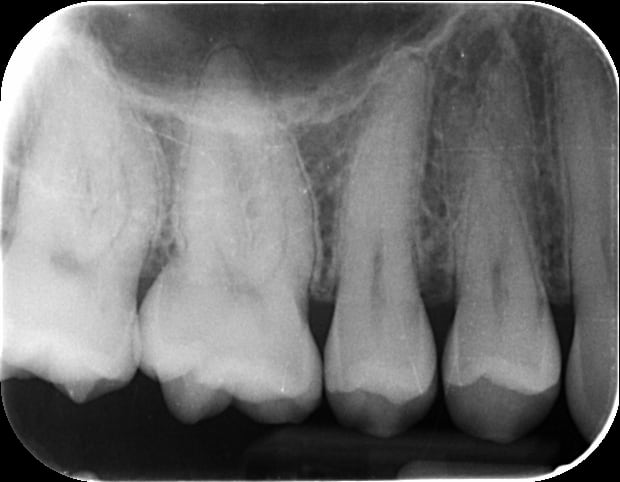

Radiologiquement, tout semble sain, je serais très très étonné que le problème soit dentaire. La 16 ne semble pas cariée, les contours ligamentaires de la racine sont très nets sans aucun élargissement, je vois rarement de dents dont je suis aussi certain du bon état sur une rétroalvéolaire. Je ne peux pas éliminer à 100% une fêlure, mais il n'y aurait pas des douleurs jugales dans ce cas là.

Le sinus semble clair, même si là encore je ne peux pas éliminer à 100% un encombrement sinusien entrainant une légère sensibilité dentaire, mais ça ne fait pas partie des symptômes que tu listais.